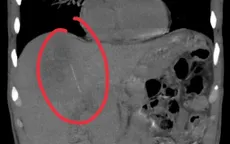

Nuốt tăm tre, người bệnh suýt mất mạng vì áp xe gan sâu

VTV.vn - Thói quen ngậm tăm sau ăn tưởng vô hại có thể khiến dị vật xuyên thủng đường tiêu hóa, di chuyển vào gan gây áp xe nguy hiểm, đe dọa tính mạng nếu phát hiện muộn.